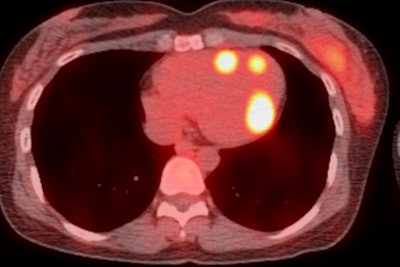

![Axial Ga-68 DOTATATE PET/CT image for the same patient demonstrates the focal tracer uptake localized to the interventricular septum (maximum standardized uptake value [SUVmax] = 24).](https://img.auntminnieeurope.com/files/base/smg/all/image/2020/10/ame.2020_10_27_16_51_9149_2020_10_27_mol_insider_Renfrew_figure2.png?auto=format%2Ccompress&fit=max&q=70&w=400)

"While hepatic and nodal metastases are commonplace at the time of NET diagnosis, cardiac metastases are found much less frequently," explained Renfrew, who is a postgraduate year 5 (PGY-5) radiology resident. "The diagnostic criterion of cardiac metastasis is focal tracer uptake in the myocardium."

A total of 16 cardiac lesions were located in the left ventricle, eight were in the interventricular septum, and five were in the right ventricle.

The average SUVmax of these lesions was 9.2 (range, 2.6-24.1), and the Krenning score was 2-4. The average SUVmax of blood pool was 1.2 (range, 0.5-2.4). The average lesion to blood pool SUV ratio was 8.3 (range, 2.6-18.2).